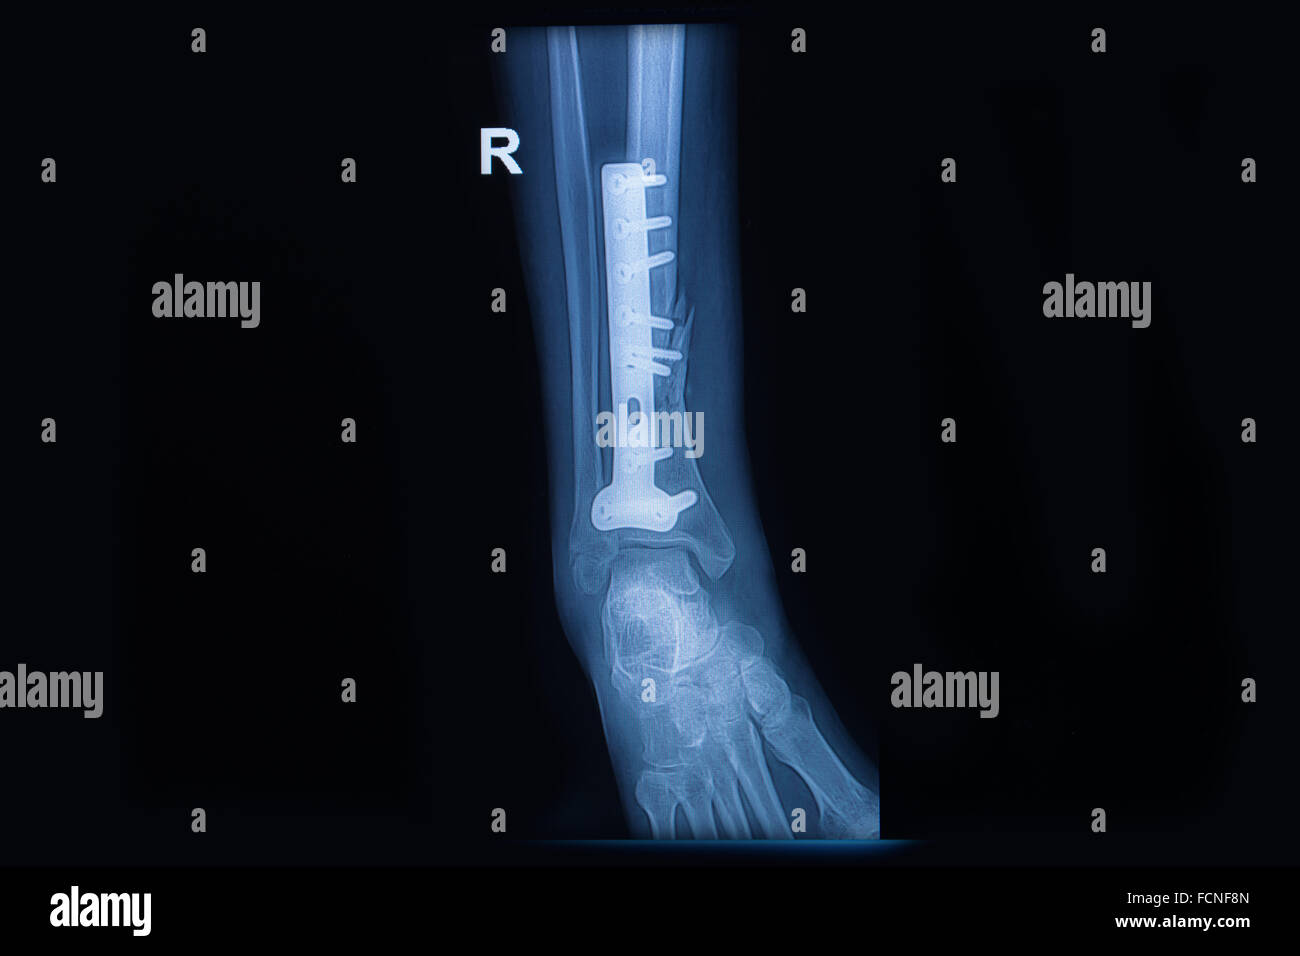

Rx Fractura En Talon - El diagnóstico se realiza mediante radiografía y, de. El calcáneo es el hueso que más frecuentemente se fractura del tarso, el 75% de las fracturas son intraarticulares y su tratamiento sigue siendo hoy en día objeto de debate. Web las fracturas calcáneas producen diferentes señales y síntomas, dependiendo de si son fracturas traumáticas o por sobrecarga. Web cuando el calcáneo.

Rx Fractura En Talon - El diagnóstico se realiza mediante radiografía y, de. Presenta tres carillas articulares (1, 2, 3) para el. Ángulos de gissane (blanco) y böhler (negro). En los protocolos actuales el tratamiento conservador está reservado. Web cuando el calcáneo está fracturado, el talón está dolorido y, por lo general, el pie y el tobillo están hinchados y no soportan el.

Rx Fractura En Talon - Ángulos de gissane (blanco) y böhler (negro). Web las fracturas del calcáneo (hueso del talón) se suelen producir como resultado de una gran fuerza. En los protocolos actuales el tratamiento conservador está reservado. Presenta tres carillas articulares (1, 2, 3) para el. El calcáneo es el hueso que más frecuentemente se fractura del tarso, el 75% de las fracturas son.

Rx Fractura En Talon - El calcáneo es el hueso que más frecuentemente se fractura del tarso, el 75% de las fracturas son intraarticulares y su tratamiento sigue siendo hoy en día objeto de debate. El diagnóstico se realiza mediante radiografía y, de. Ángulos de gissane (blanco) y böhler (negro). En los protocolos actuales el tratamiento conservador está reservado. Presenta tres carillas articulares (1, 2,.